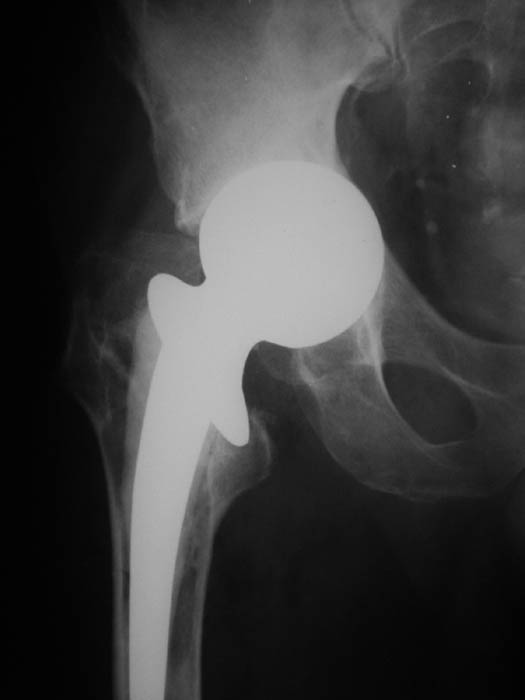

Мужчина, 77 лет. В 2000 г. по поводу субкапитального перелома шейки бедренной кости произведена операция эндопротезирования головки. На последних рентгенограммах обнаружена протрузия головки эндопротеза.

В настоящее ведет активный образ жизни, продолжает работать.Предполагается замена протеза на тотальный ревизионный. Интересуют предложения по восстановлению костной массы вертлужной впадины.Заранее благодарю!С уважением,А.В.ВладзимирскийДонецкий НИИ травматологии и ортопедииДонецк, Украина

Такой исход не редок при применении однополюсного эндопротеза. При ревизионном эндопротезировании с пластикой вертлужной впадины применяем кольца Мюллера или Бурхшнайдера. Основная проблема - найти адекватное количество пластического материала. Приходится комбинировать ауто- и аллотрансплантаты. Среди аллотрансплантатов лучше использовать лиофилизированные губчатые и частично деминерализованные, в наиболее нагружаемых зонах кортикальные. На сайте 13 ГКБ (gkb13.webzone.ru) г. Москвы в разделе "публикации" найдете несколько статей, посвященных этой проблеме.

Решение о замене на тотальный ревизионный протез бесусловно правильное, если пациент в таком возрасте сохранный. Дефект под антипротрузионным кольцом возможно заполнить аутотранстплантатом из крыла подвздошной кости большими фрагментом или же костной крошкой из него. Если у пациента есть проблемы со здоровьем, то возможен и вариант рекомендаций по ходьбе с костылями и уменьшении нагрузку на ногу, что предотвратит дальнейшую протрузию. С уважением Е.А.Волокитина.

Желательно применить аллакость - фрагмент головки или мыщелков бедра. Опилить и закрыть дно, затем набить костные чипсы с хорошим уплотнением. Если получится плотно, то можно установить безцементную чашку.

при наличии действительного желания помочь пацменту, показана пластика дна вертлужной впадины деминерилизованной крышкой, трансплантатом, теменной кости ( выпускают фирмы Италии и нашего ЦИТО, п.с. У. ЦИТО дешевле. ), пластика показана при наличии опыта, и замены трансплантата на бесцементный эндопротез, с костной пластикой и готовностью поставить ножку Вагнера